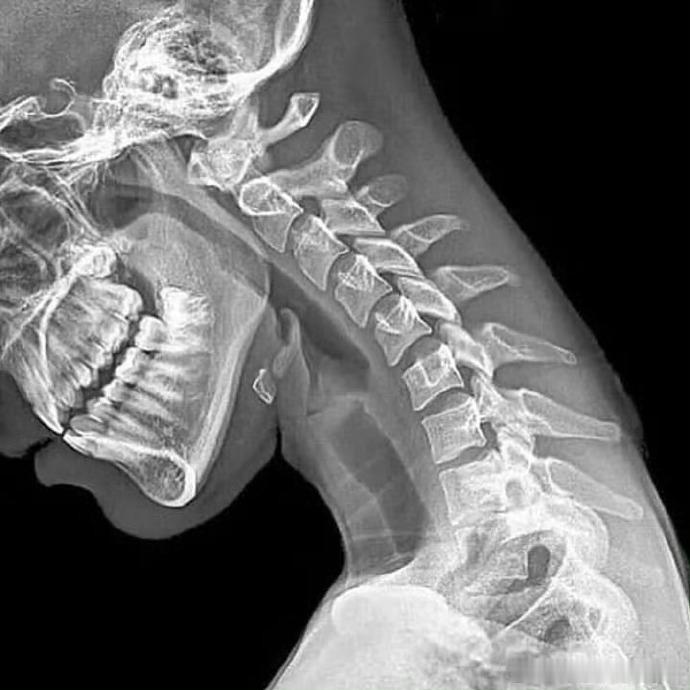

颈椎病 为啥不要总低头?来看对比你就知道了👇🏻👇🏻我们的颈椎,本来正常的生理曲度,应该呈现出轻微的前凸,是图1的样子。但当你低头的时候,颈椎不得不向后弯曲,时间一长,颈椎压力过大、肩颈不适,很多人的颈椎曲度变直/反弓,也是这么来的健闻登顶计划运动康复